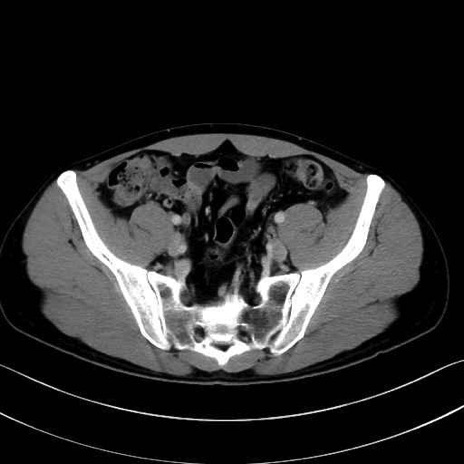

梨状筋 (Piriformis)